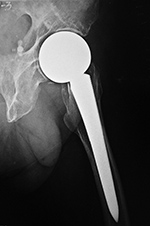

| Unipolar hip hemiarthroplasties (endoprostheses) |

Unipolar hip hemiarthroplasty (endoprosthesis) with a cemented femoral component |

Modular non-cemented unipolar hip hemiarthroplasty (endoprosthesis) |

| These are single piece prostheses press fit into the native acetabulum and the native femur. From Benjamin, 1994 |

Note the collar abutting the femoral calcar. From Benjamin, 1994 |

Note the collar abutting the femoral calcar. |